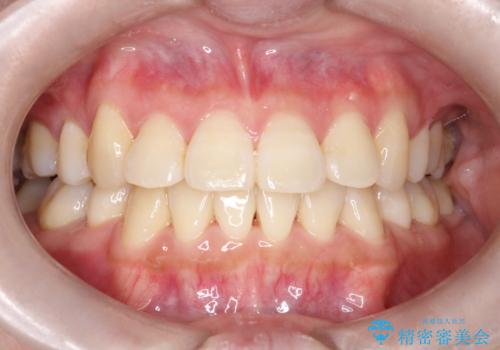

【過蓋咬合・正中離開・奥歯のズレでお悩みの方必見】非抜歯矯正症例(顎骨の成長を利用)